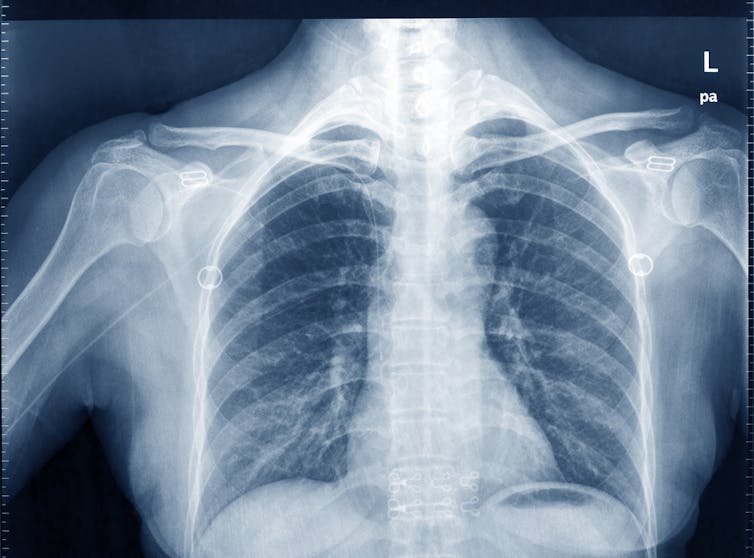

‘X-rays’ or planar radiography

This is still the most common, widely-available and simplest form of medical imaging, often used to see a broken bone. X-rays are actually photons, or tiny packets of energy (referred to as ionizing radiation) and form part of the electromagnetic spectrum (as does visible light, microwaves and radio waves).

As an x-ray beam passes through human tissue, these x-ray photons can be absorbed and deflected by dense tissue structures such as bone and may not exit the body. Other x-ray photons may encounter tissue that is less dense (such as muscle) and are able to pass through this quite easily and exit the body.

The exiting x-ray photons then reach a digital imaging receptor or detector where they provide a tissue density pattern for the digital receptor to convert into the x-ray image (or radiograph) that we are familiar with.

Dense tissue such as bone that has attenuated the x-ray beam appears dense or white; less dense tissue such as lungs that are filled with air appear less dense or dark, which we observe with a “chest x-ray”. Other tissues in the human body have densities between these two extremes and appear on an x-ray image as different shades of grey.

Patients should be reassured this form medical imaging is straight-forward, and there should be no risk or danger from the radiation when used correctly.